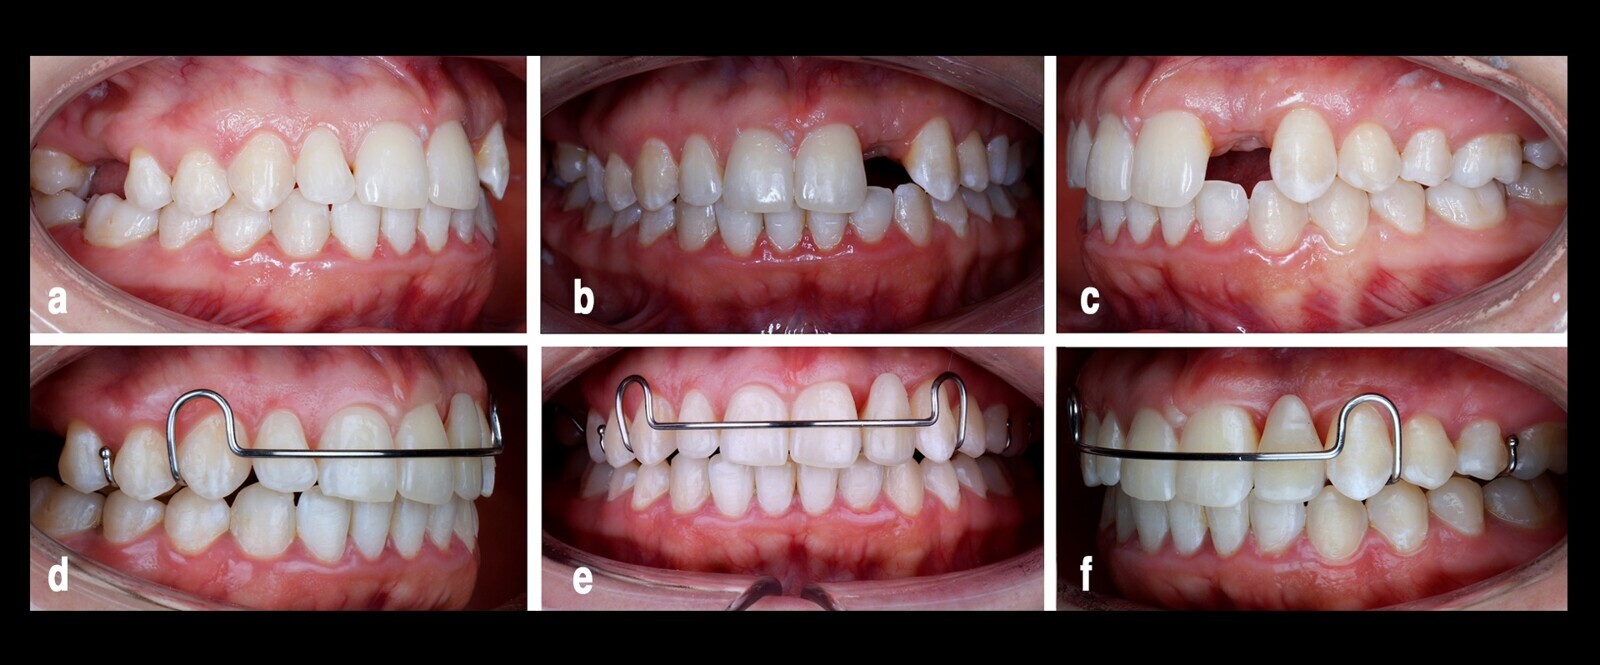

Figura 1. Radiografías iniciales. En la panorámica general (a) y en la imagen más detallada en 3D (b) se observa microdoncia aislada en el diente 22 e infraoclusión en el diente 23 respecto a su posición ideal y acortamiento radicular por trauma.

Paciente sin antecedentes sistémicos relevantes con maloclusión de clase II, mordida profunda anterior, diastema en dientes anteriores superiores con microdoncia aislada en el diente 22 (incisivo superior lateral izquierdo), forma cónica y movilidad dental3. El diente 23 presentaba infraoclusión con relación vestibular y mesial a su posición ideal. Al análisis radiográfico presentó acortamiento radicular por trauma oclusal a nivel de los incisivos superiores. En el arco inferior tenía una profundidad moderada de la curva de Spee, apiñamiento dental moderado y diente 38 impactado horizontal (Fig. 1).